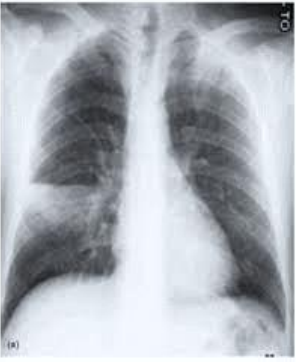

Paciente do sexo masculino, 52 anos, hipertenso e com hipotireoidismo, em tratamento regular, comparece à UBS onde você está atuando com queixa de tosse produtiva de 7 dias e evolução associada a quadro febril que se iniciou há 5 dias. Nega internações prévias. Ao exame físico, apresenta-se em regular estado geral, febril, acianótico, Glasgow 15/15. Ausculta pulmonar: murmúrio vesicular conservado com estertor crepitante em terço médio do pulmão direito. Ausculta cardíaca: BRNF 2T. Abdômen: flácido, hiper-timpânico RH presentes. Sinais vitais: FC 105; FR 25; temperatura axilar: 38,1; SatO2 96%; PA 115/70. O paciente possui exames laboratoriais realizados no dia anterior, assim como radiografia de tórax, apresentada a seguir. Leucócitos 14800 MM3; neutrofilos 85%; bastões 5%; PCR quantitativo 18mg/dl; ureia 55 mg/dl; Creatinina 1 mg/dl.